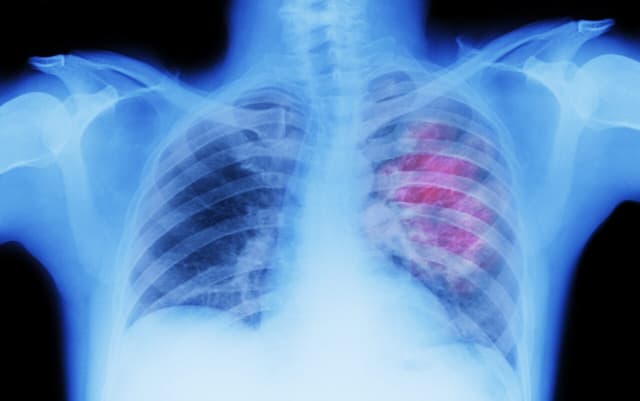

Ung thư phổi là một trong những bệnh K phổ biến và có tỷ lệ tử vong cao. Tuy nhiên, trong những năm gần đây, với sự phát triển vượt bậc của y học hiện đại, quan điểm này đang dần thay đổi. Nhiều bệnh nhân đã được kéo dài sự sống, thậm chí đạt […]

Ung thư phổi (UTP) là một trong những căn bệnh ung thư phổ biến không chỉ ở Việt Nam mà còn trên thế giới. Với số lượng người mắc đang tăng lên, UTP là nguyên nhân gây ra hàng nghìn ca tử vong mỗi năm. Hãy cùng tìm hiểu những thông tin quan trọng cần […]